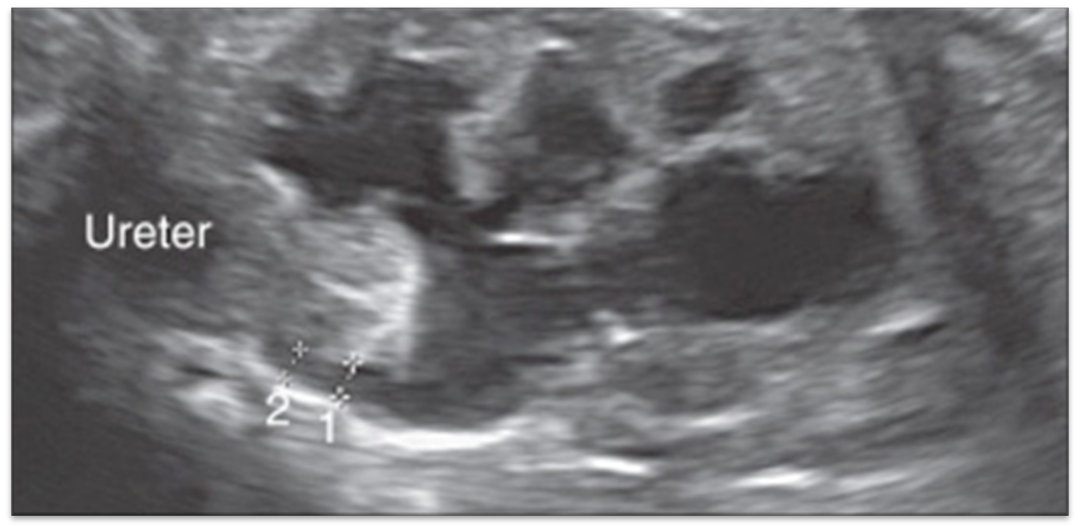

UVJ Obstruction